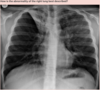

HPC: A 45-year-old man presented to ED with dyspnoea, chest pain, palpitations, and cough. Erythema nodosum on the shins were also noted.

What is the likely diagnosis in this patient?

A

Answer: Sarcoidosis

Sarcoidosis is characterised by bilateral hilar adenopathy and certain clinical features such as erythema nodosum. Diagnosis is made in consideration of the clinical picture and CXR, alongside the gold-standard diagnostic tool of bronchoscopic biopsy which would show non-caseating granulomas with giant cells, asteroid bodies, and Schaumann bodies.